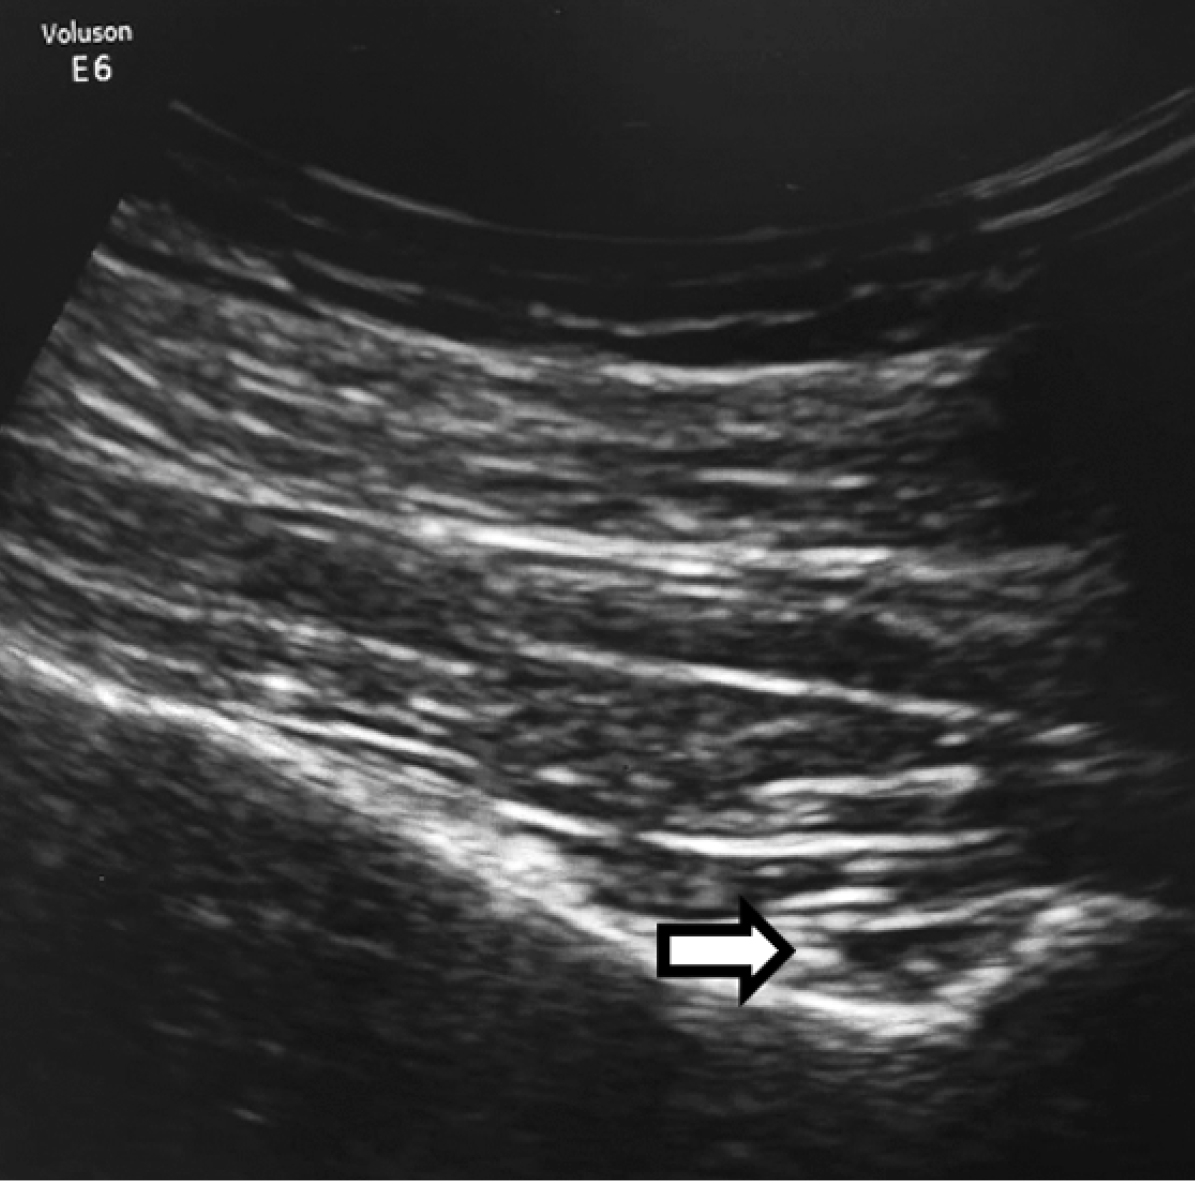

During the course of hyperbaric oxygen therapy, the patient developed new shoulder pain, raising concerns about the possible progression of AVN to other joints. MRI of both shoulders confirmed the diagnosis of bilateral stage III AVN in the humeral heads (Figure 2). At this point, the patient was referred to our clinic for further evaluation and pain management.

Figure 2. MRI revealing multiple areas of humeral head avascular necrosis (marked with white arrows)